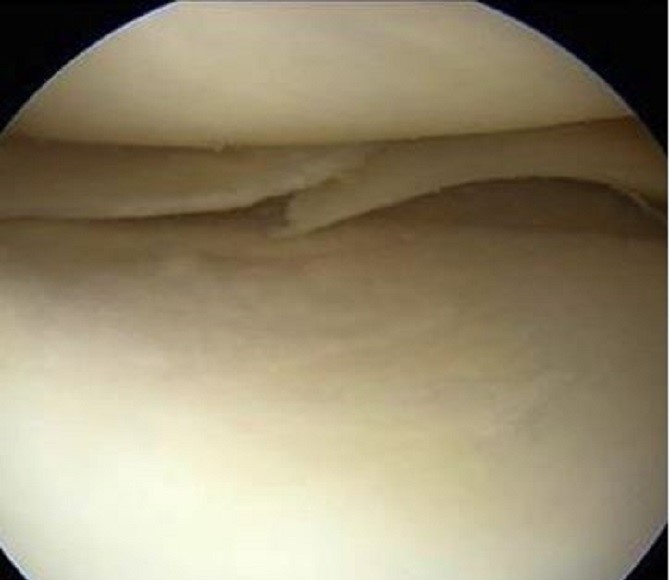

L'artroscopia di ginocchio è una delle procedure chirurgiche più comunemente eseguite. Questo intervento normalmente viene effettuato in anestesia locale (anestesia che si ottiene praticando due o tre punture di anestetico locale direttamente nel ginocchio che renderanno insensibile solo l'articolazione) ed in regime di Day Hopital ( dimissioni in giornata).

Una microcamera sarà inserita attraverso una piccola incisione della pelle. Ciò fornisce una chiara visione della parte interna del ginocchio. Il chirurgo ortopedico inserirà strumenti chirurgici miniaturizzati attraverso un altra piccola incisione per rimuovere o per riparare la lesione del menisco.Un intervento chirurgico per una lesione meniscale in artroscopia in media dura 10 - 20 minuti.